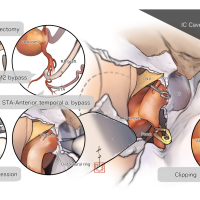

術後イラストシリーズ

脳神経外科速報 増刊号 基本手技のバリエーション(メディカ出版) 寄稿シリーズ

OPExPARKコンテンツ・脳神経外科速報寄稿シリーズ